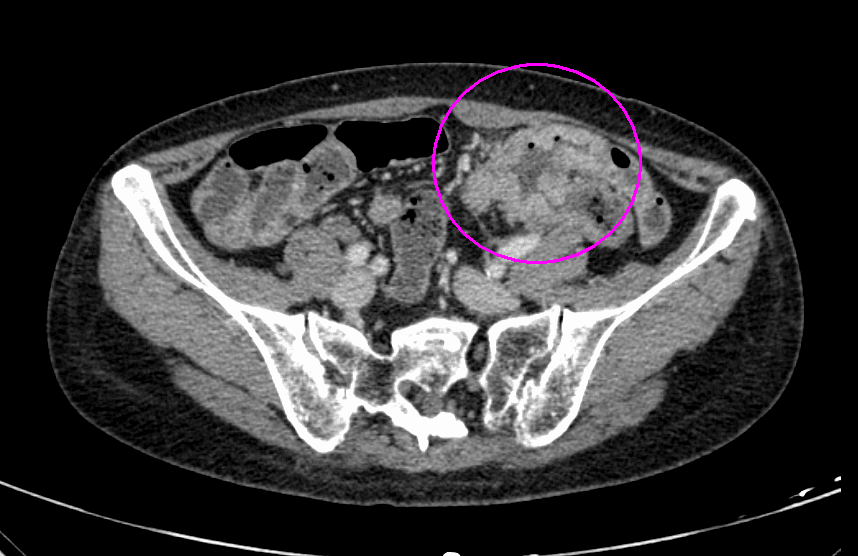

CT検査

CT検査画像